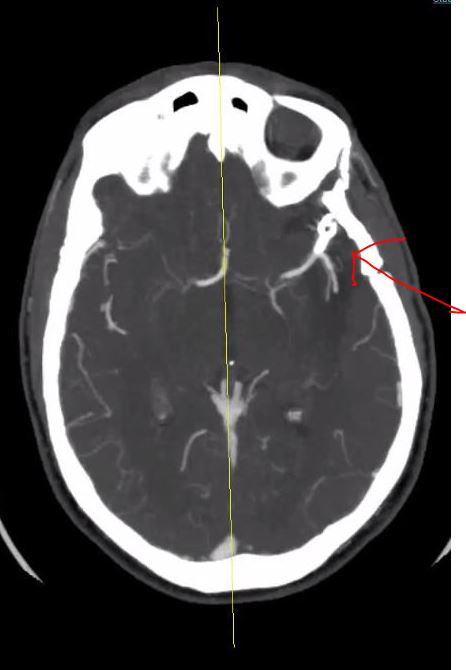

I had my latest scan and checkup this year. My titanium clip is still in place. My rupture has not leaked or expanded. and there are no obvious new formations or bulges detected. I do not have any restrictions and I can continue my travel goals and enjoying life day by day. Today is a day where I reflect and I am thankful that I can love another day and enjoy my passions and life that might have ended so quickly before.